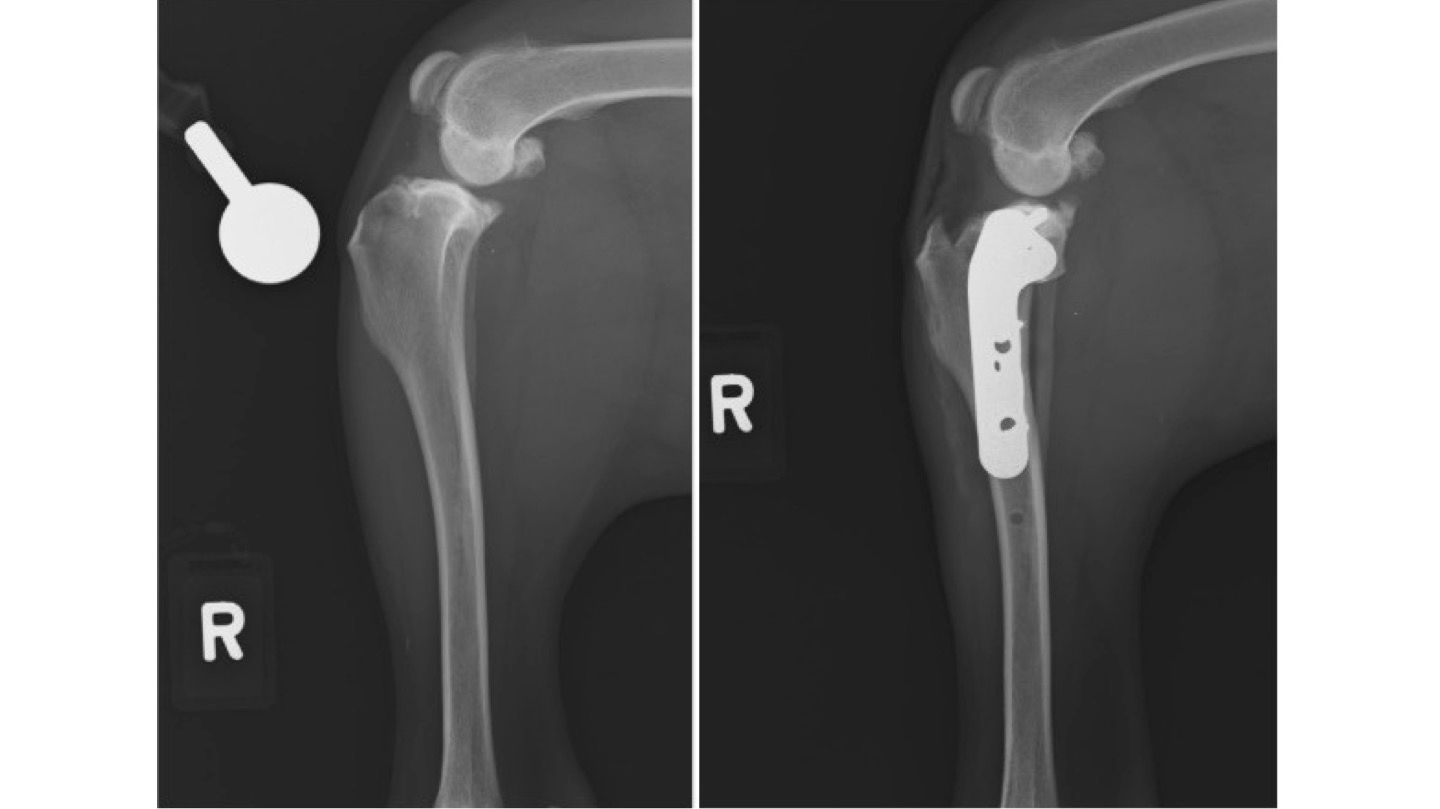

TPLO Surgery (Tibial Plateau Leveling Osteotomy)

For dogs with torn cranial cruciate ligaments (the equivalent of an ACL tear), we offer TPLO surgery, a commonly recommended procedure to restore knee stability.

- TPLO works by cutting and rotating the top segment of the tibia (shinbone) to correct its angle, then securing it with a plate and screws

- This changes the biomechanics of the joint, allowing t he dog to bear weight normally without relying on a damaged ligament

- TPLO is celebrated as the gold standard for cruciate ligament repair, offering excellent long-term outcomes, faster recovery, and high return-to-function rates